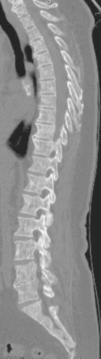

Clinical caseA 72-year-old Caucasian woman with a history of diverticulosis, surgically-corrected lumbar hernia and plurisegmental degenerative osteoarticular disease is reported. There was no background of allergies, smoking or alcoholism and she was taking only analgesic medications. In May 2012, she was admitted for acute diverticulitis. During her hospital stay the lower back pain worsened and so a computed tomography (CT) scan of the lumbar spine was performed which documented diffuse osteopenia and multiple scattered osteosclerotic lesions on vertebrae, the sacrum and the iliac bones (Figure 1). After discharge and with a presumptive diagnosis of occult neoplastic disorder, she was referred to her doctor for further studies.

Several medical tests were performed including blood analysis, endoscopic and imaging exams but none showed relevant changes. In September she started with persistent diaphoresis with no fever or any symptoms suggestive of an infectious focus, anorexia and a quantified weight loss. The blood tests revealed slightly elevated levels of alkaline phosphatase (162U/L) and lactate dehydrogenase (LDH – 454U/L). She was admitted again and a CT body scan was performed (Figure 2) which showed osteolytic lesions, in addition to the diffuse osteosclerotic lesions previously documented, without expansive features, spread throughout the axial skeleton, that were assumed to be bone marrow sclerosis phenomena. Diaphoresis was associated to a pharmacological iatrogenic effect and the weight loss to a reactive depression. She was discharged and referred to our Internal Medicine Department.